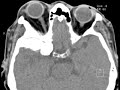

Sphenoid Wing Meningioma

These images demonstrate a hyperdense infiltrative mass located in the anterior right middle cranial fossa with impressive reactive hyperostosis involving the greater sphenoid wing with extension into the right orbital apex, skull base foramina, and right sphenoid sinus. There is hypoattenuation in the anterior right temporal lobe likely reflecting gliosis. This mass was favored to represent a meningioma, although metastasis and primary bone tumors were also considered in the differential. Meningiomas are the most common primary intracranial tumor, are more common in females, usually appear hyperdense on CT, and may calcify. They usually avidly enhance and can have reactive hyperostosis of the adjacent calvarium as seen here.